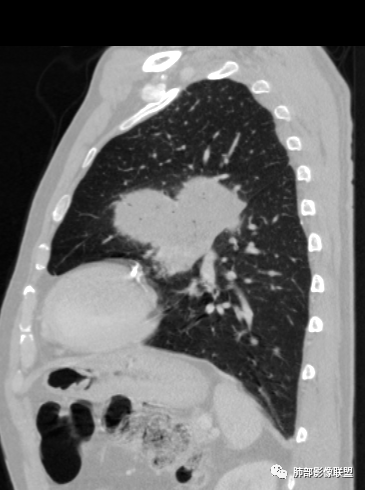

左肺上叶大肿块,膨胀性生长,边界清,密度较低,见部分坏死区,强化弱,肿块见支气管充气V扩张征,分布僵直,枯树枝特点,另一个重要特点血管造影征,淋巴瘤,肿块长轴与胸膜平行,与隐球菌鉴别,隐球荚膜抗原检查,明确诊断经皮肺穿刺。另胸膜钙化(问诊既往有无患胸膜炎病史)。

左肺上叶胸膜下肿块,宽基底与胸膜相连,跨叶裂,边缘清晰膨隆,其内支气管充气,部分扩张、僵直,无明显强化,血管造影征,考虑淋巴瘤,鉴别腺癌

左肺胸膜下巨大占位,跨叶裂,宽基底与胸膜相连,胸膜钙化,平扫密度较低,强化不明显,可见内部血管显影,支气管充气征和扩张,考虑为恶性,倾向于淋巴瘤

左侧胸腔巨大肿块,跨叶生长,临近胸膜钙化,边缘模糊,可见支气管影,定位肺内,增强后轻度强化,边缘见血管影,考虑淋巴瘤,鉴别肉瘤

左肺上叶胸膜下肿块,膨胀性生长,边界清晰,密度不均部分坏死,未见强化,病灶内支气管迂曲扩张,病灶长轴与胸膜平行,胸膜下脂肪间隙存在,胸膜钙化,考虑放线菌?毛霉?鉴别淋巴瘤

支持淋巴瘤,左上肺大肿块,有分叶,边缘光整,病灶内密度不均,可见支气管扩张征,增强后可见血管影征。周围肺野清晰。

左肺上叶肿块,宽基底与胸膜相连,跨叶裂,边缘清晰膨隆,可见小分叶,其内支气管充气,部分扩张、僵直,呈枯枝征,支气管达边征,增强无明显强化,可见血管造影征,考虑恶性病变,淋巴瘤,鉴别粘液腺癌。

大肿块,边缘光滑,深分叶

近端支气管堵塞、推移为主

部分类似于脐凹征

内部支气管扩张

肺动脉推移为主,边缘部分进入

大肿块、表面光滑但深分叶,肺门侧支气管堵塞

1)部位:周围型或中央型软组织肿块,以周围型为多见,且肿瘤多位于肺上叶。如本例:该肿瘤位于左肺上叶。

2)大小及形态:由于本病恶性程度高,早期症状不明显,发现时肿块均较大。如本例病变巨大。

3)肿块边界和边缘:多较清楚,呈圆形、类圆形,且由于肿块生长速度不均匀,可见分叶,毛刺少见。有报道肿块周围毛玻璃影是多形性癌特征表现。

4)密度:肿块平扫为软组织密度,由于体积较大,内部常见大片状坏死,可出现不规则厚壁空洞或坏死内多发无壁小空洞,坏死多不均匀:坏死灶内可见如柳絮样的斑片样强化灶,坏死边缘与非坏死区分界不清本例坏死较明显,密度不均匀。

5)肿瘤强化方式:肺部恶性肿瘤强化程度与其血供丰富程度相关,血供丰富多强化明显,反之则较差。由于PSC 周边实性部分富血供及内部黏液变性、坏死,增强后肿块多数呈轻-中度边缘环形强化或不均匀小斑片状强化。国外学者对照病理发现肿瘤细胞或胶原组织增强扫描时强化,无强化的低密度区代表了黏液样变性区和出血坏死区。